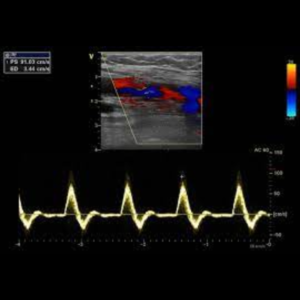

Ecografía Doppler Arterial

La ecografía Doppler arterial es un estudio de ecografías que estudia las diferentes ramas arterias de miembro superior o inferior, evaluando su calibre y descartando la presencia de placas ateromatosas o estrechez que indiquen un flujo lento, por lo tanto descarta insuficiencia arterial.